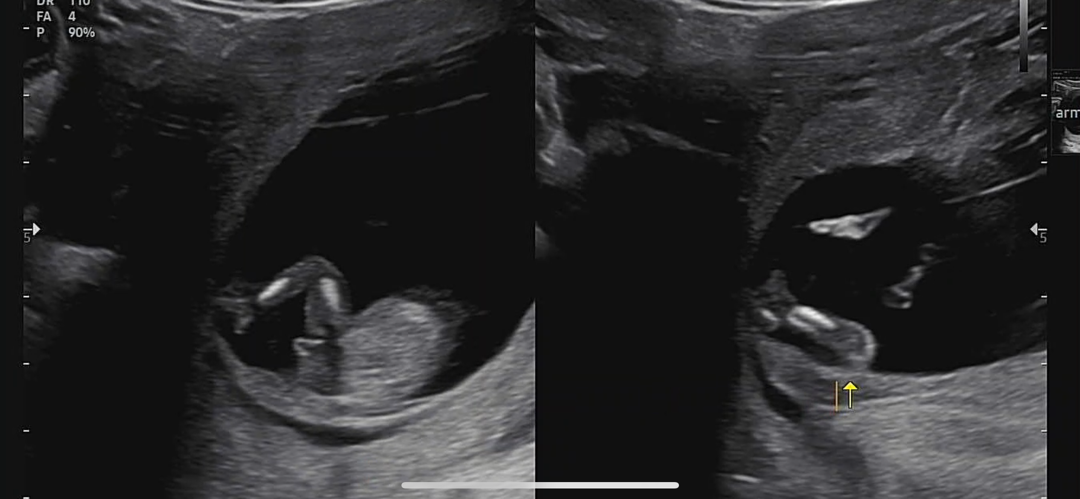

니프티보다 빨랐던 12주차 초음파 성별ㅋㅋ

보통 16주 지나서 안전하게 20주에 성별 확실해진다구 하잖아여… 저는 12주차에 정기검진갔다가 그냥 빼박100% 라고 알려주셨어여 ㅎㅎ 처음엔 왜이리 확신하시지 싶었는데 동영상 돌려보니… 이렇게 확실해도 되나 싶네여ㅋㅋㅋ 애기가 가릴 생각이 없다구 의사쌤이 그러시더라구여ㅋㅋㅋ 니프티보다도 빠른 결과였답니당…:)